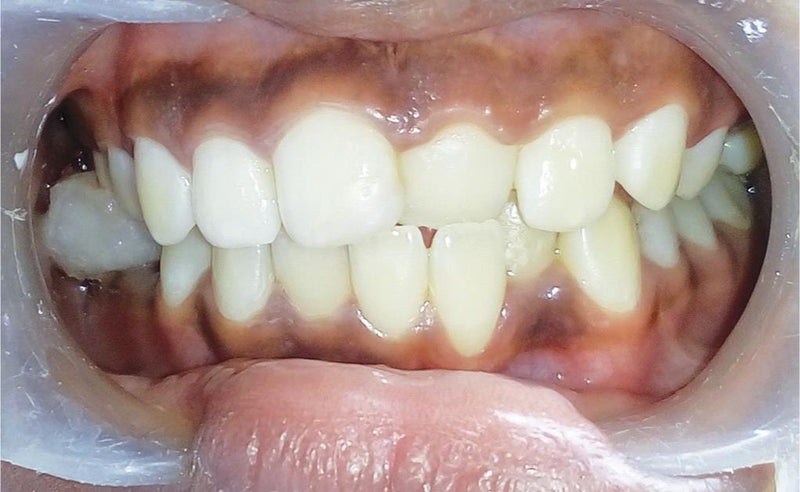

انواع کراس بایت (کراس بایت قدامی)

کراس بایت قدامی